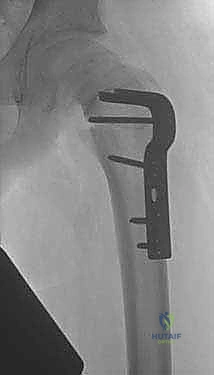

الخطوة الخامسة: التثبيت الصلب (Rigid Fixation)

للحفاظ على هذا الوضع الجديد حتى يلتئم العظم، يتم استخدام شرائح ومسامير معدنية قوية جداً. قديماً كانت تُستخدم الشريحة ذات الشفرة (Blade Plate)، ولكن اليوم، يستخدم الأستاذ الدكتور محمد هطيف أحدث أنظمة التثبيت العالمية مثل (Dynamic Hip Screw - DHS) أو الشرائح التشريحية المغلقة (Locking Plates) التي توفر ثباتاً مطلقاً وتسمح بالتئام أسرع.